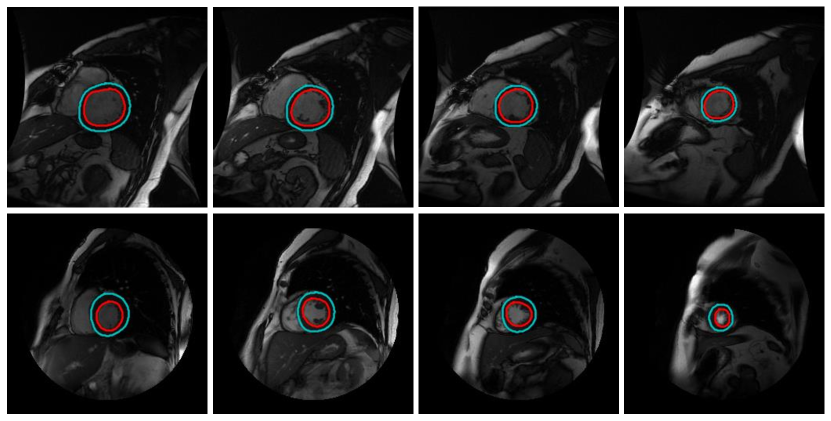

Good results: Selected prediction examples from the Sunnybrook test set are shown in Figure 8. As shown in the figure, our model is able to produce accurate results on most slices of left ventricular MRI.

![]() |